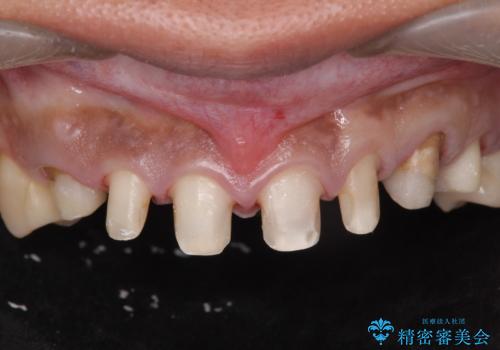

複数箇所コンポジット充填された前歯をセラミック治療

- コンポジットレジンの充填箇所がすり減ってしまい、形の悪くなった前歯の治療を希望され来院されました。

充填部位が大きく、再度充填をするには神経と近くなり抜髄のリスクが高まるため、劣化の少ないセラミックでフルカバーするセラミッククラウン治療を行うこととしました。